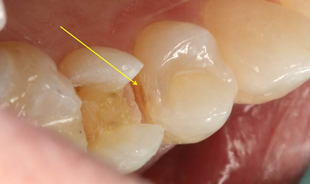

Based upon the patient’s history, compliance and desire to avoid costly dental treatment, a preventive treatment option was offered in an attempt to remineralize the interproximal lesions. The protocol involved an office fluoride varnish application with 3M ESPE Vanish Varnish and use of 3M ESPE Clinpro 5000 toothpaste at home. The areas were rescanned with The Canary System 6 months later with no reduction in the CN. Further review of risk factors revealed that the patient continued to consume one to two carbonated sugared drinks per day, which likely interfered with the remineralization process. Based upon the Canary findings, tooth #4 underwent restorative treatment. As soon as the mesial portion was opened, a large lesion was found which extended beyond the DEJ (Fig. 5a). Visual examination of the distal surface of tooth #5 revealed an area of brown decalcification with no obvious pathology (Fig. 5b). The distal surface of tooth #5 was opened (indicated with a yellow arrow) and a large lesion into the dentin was found (Fig. 5c).

Fig. 5b #5 distal decalcification